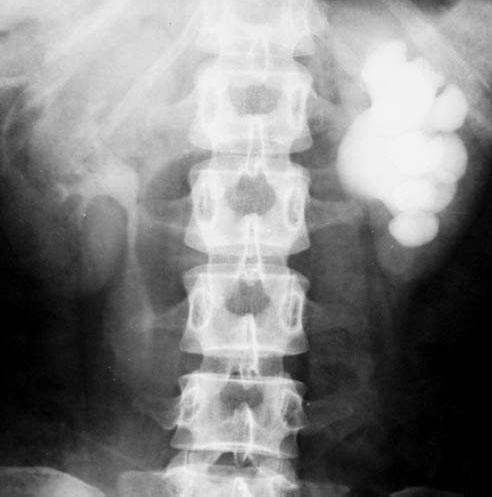

照片名称:右股骨正侧位x线片